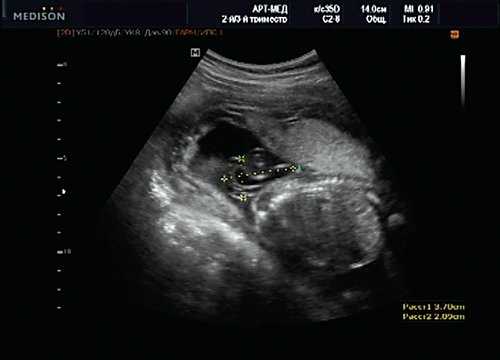

Некоторые ультразвуковые измерения в I триместре обязательны для выполнения. В большинстве случаев гестационный возраст до 15 нед с определенной степенью точности оценивают по показателям бипариетального размера (БПР) и копчико-теменного размера (КТР) (рис. 1). В дальнейшем эту информацию дополнять не будут, а использовать будут в основном для установления задержки внутриутробного развития, при планировании обследования по поводу врожденных аномалий и послеродовых осложнений. УЗИ на сроках между 11 нед 0 дней и 13 нед 6 дней необходимо постоянно сравнивать с данными обследования на сроках между 7 и 10 нед. Таким образом, УЗИ в I триместре должно помочь обнаружить ряд аномалий развития плода, например триплоидию [1].

В начале 90-х годов прошлого века в практику был внедрен метод измерения толщины воротникового пространства (ТВП) в I триместре беременности, и к настоящему времени его считают показателем не только анеуплоидии, но и широкого спектра наследственных синдромов и пороков развития [2]. K. Николаидес (K. Nicolaides) с группой исследователей предложили новую модель скрининга на анеуплоидию и установили правила использования этого метода, в частности необходимость применения кривой обучения, проведения аудита, качественного (процедура оценки качества изображений) и количественного (медиана, дельты-ТВП и т.д.). Фонд медицины плода (Fetal Medicine Foundation) стандартизировал предложенный ими клинический протокол и установил правила сертификации для повышения качества медицинской помощи и уменьшения изменчивости результатов данных скрининга [3, 4]. Измерение ТВП можно проводить вручную (рис. 2a) или полуавтоматически (рис. 2b), чтобы результаты измерений были более воспроизводимыми. Кроме того, компания Samsung разработала дополнительный метод измерения показателей ТВП - 5D NT, позволяющий точно выявить срединно-сагиттальную плоскость и улучшить оценки по шкале Германа (Herman score).